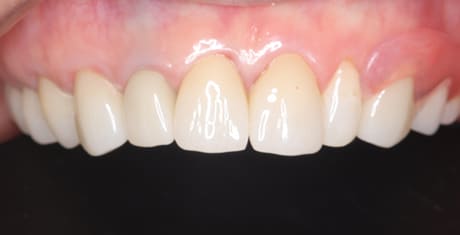

治療前後の口元の比較

こちらは、口を少し開いた時の治療前と治療後の

口元です。

正面から見た時にクラスプが目立たないように、

歯ぐきになじむ素材にて入れ歯を製作し、痛くなく自然に馴染み快適に生活を送れるようになりました。